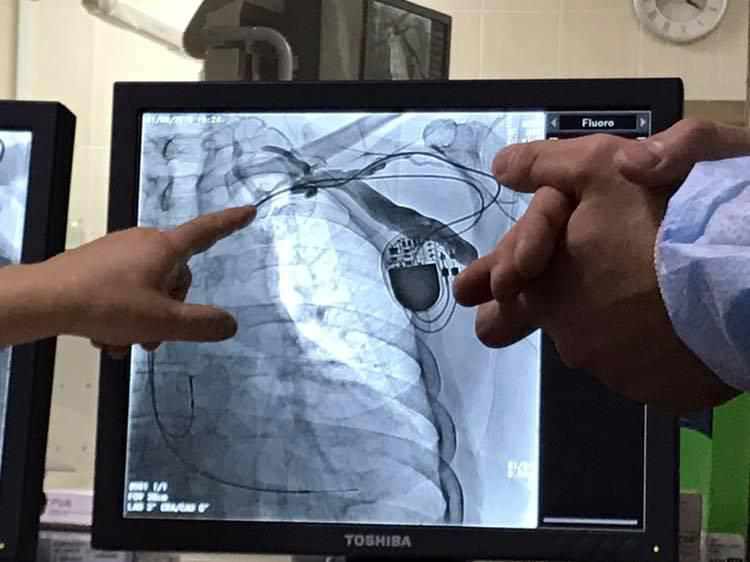

У Полтавській обласній лікарні чоловіку зробили унікальну операцію на серці. ФОТО

Ми ж з радістю повідомляємо, що цього дня, за допомогою Валерія Залевського, електрофізіолога, завідувача відділення хірургії складних порушень серцевого ритму та електрокардіостимуляції з рентгенопераційною Національного інституту серцево-судинної хірургії імені М. М. Амосова, у катетеризаційній лабораторії нашого відділення інтервенційної радіології успішно виконано унікальну для Полтавщини операцію – імплантацію трикамерного автоматичного кардіовертер-дефібрилятора.

– Сьогоднішня операція була складною, у першу чергу для лікарів, а для цього пацієнта – це один з етапів процесу лікування. У нього ще є передсердна тахікардія і йому необхідне лікування порушення ритму, тобто його чекає абляція. Поки що ми виконали втручання з нульовою травматизацією, яке не потребує відкриття грудної клітки. Ресинхронізація у різних пацієнтів дає різні результати. Є і такі випадки, коли пацієнти повертаються до здорового життя. Даний пацієнт не потребує якихось особливих рекомендацій по способу життя, достатньо дотримуватися водного балансу, стежити за вагою.